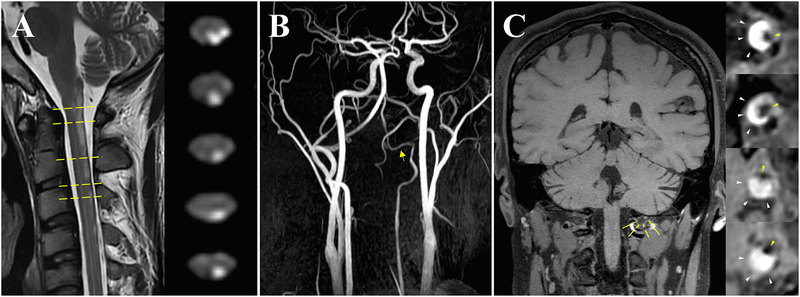

自发性脊髓梗死(SCI)是一种罕见的严重致残疾病,约占所有卒中的1%,最可能的机制是特发性动脉粥样硬化(68%),椎动脉夹层仅占3%。脊髓血供更加丰富,包括两条脊髓后动脉和更广泛的侧支网络,自发性椎动脉夹层很少影响脊髓,即使影响,也总是累及脊髓前动脉。本文报告一例由椎动脉夹层引起的长节段后部脊髓梗死患者。 24岁男性,4天前突发左侧肢体麻木乏力,伴颈部疼痛和泌尿功能障碍,次日症状加重,无法行走,右侧肢体出现麻木和瘫痪。6个月前得过水痘,无外伤史。神经系统检查显示左侧面部和右侧肢体触觉减弱,左肢振动觉减弱,左侧肢体肌力3级,右侧肢体肌力4级,双侧巴宾斯基征阳性。 脊柱核磁(MRI)显示C1-C5脊髓水平出现高信号病灶,位于颈髓左后外侧柱,甚至中央管周围区域(图1A)。尽管左椎动脉直径较小(类似于椎动脉发育不良),但MRA没有左椎动脉狭窄的证据(图1B,黄色箭头)。然而,头颈部血管壁磁共振成像显示左椎动脉V3段长节段夹层的典型特征,伴有壁间血肿和残余腔(图1C)。患者接受口服阿司匹林100mgqd和阿托伐他汀40mgqd治疗。住院一周后,患者出院。出院时,感觉迟钝已经缓解,但肌力仍然和以前一样。 (A)矢状T2和轴向DWI显示C1-C5水平急性脊髓梗死,影响左后外侧柱,甚至脊髓中央管周围区域。(B)MRA显示左椎动脉直径较小(类似于椎动脉发育不良),没有狭窄或夹层的证据(黄色箭头)。(C)高清血管壁核磁:轴位图像显示左椎动脉的壁间血肿(白色箭头)和残余管腔(黄色箭头)。椎动脉的夹层很少影响脊髓,脊髓后动脉的受累更是少见。本病例报告提供了几个独特的临床见解。首先,在没有明确病因的情况下,在后部脊髓梗死患者应考虑椎动脉夹层。其次,高清血管壁核磁显示出对壁内血肿的显著敏感性,优于CTA或MRA,特别是在区分椎动脉夹层和发育异常。当在其他血管图像上未检测到特征性内膜瓣和双腔征时,这种优势尤其明显。早期诊断和识别SCI的病因至关重要,特别是对于需要紧急治疗的年轻患者。该病例有助于更好地了解自发性SCI,有助于早期和无创识别 SCI 的病因。